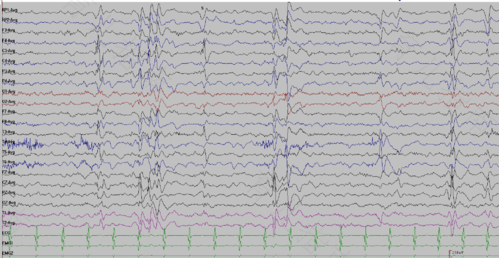

棘慢波就是脑功能出现失调,神经元异常放电引起的一种情况。慢波是脑电波波形的一种,常见于脑炎、癫痫患者,但是脑电图的诊断不能作为唯一的诊断依据,需要到医院复查,并结合其它的检查项目确定。那么正常人有棘慢波吗?

正常人不会出现棘慢波,一般情况下患有脑炎或癫痫才会有这种情况,正常人在清醒闭眼安静的状态下脑电的基本节律是8~13Hz的α波,波幅为10~100μV,正常成人以β节律为主,如果脑电波出现异常,要结合核磁共振进行检查,确诊疾病的存在。

患有癫痫会出现棘慢波,要结合其它的临床症状做出诊断,如果确诊为癫痫,必须要及时的进行治疗。平时要注意保持好的心情,而且要注意合理的饮食,平时可以补充一些维生素,在营养方面也要加强,这样才能对身体有好处。

如果出现了棘慢波,要结合以往的病史进行分析。进行动态脑电图检查,根据结果综合考虑。如果有抽搐情况,脑电图上有癫痫波发放,可以进行吃药治疗,但是平时一定要合理的做好监测,癫痫的出现原因有多种,头外伤,脑部肿,瘤脑损伤都可能造成,需要持续的进行治疗。